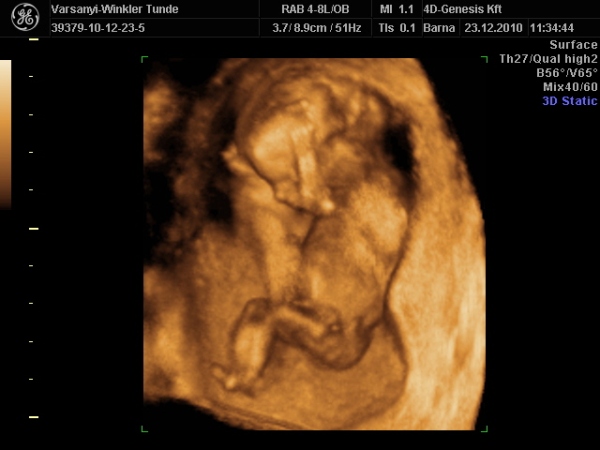

Bár tegnap a dokor bácsi azt mondta, hogy azért lassan vissza kellene vennem a lendületből, mert nem lesz jó vége. Manócska jól van, de tegnap nem tudtuk megnézni. Hasi uh-val próbálkozott, de pont úgy fordult, hogy csak a nagy kobakját láttuk

Gondolta, ha arra van a feje, akkor lentről lehet látni valamit a neméből.